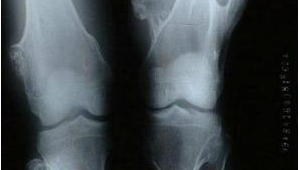

我们需要深入了解膝盖软骨瘤的特点。膝盖软骨瘤通常生长在膝盖周围的骨骼上,一般由软骨细胞异常增生形成。多数情况下,它生长缓慢,早期可能没有明显症状,或者仅有轻微的局部肿胀和疼痛。即便初期症状不严重,也不能忽视其存在对膝盖关节功能的潜在影响。

但即便如此,患者在运动过程中也必须时刻关注自身身体状况。一旦出现疼痛、肿胀等不适症状加重的情况,应立即停止运动,并及时就医。定期进行复查也是非常必要的,通过影像学检查等手段,密切监测软骨瘤的变化情况,以便根据病情调整运动计划。